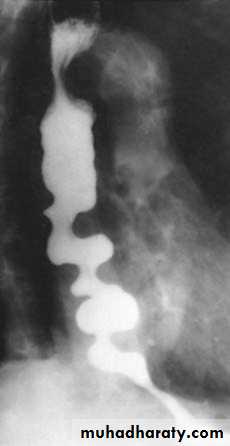

a

b

Figure8: a. bird beak

b. dilated and tortuous esophagus.